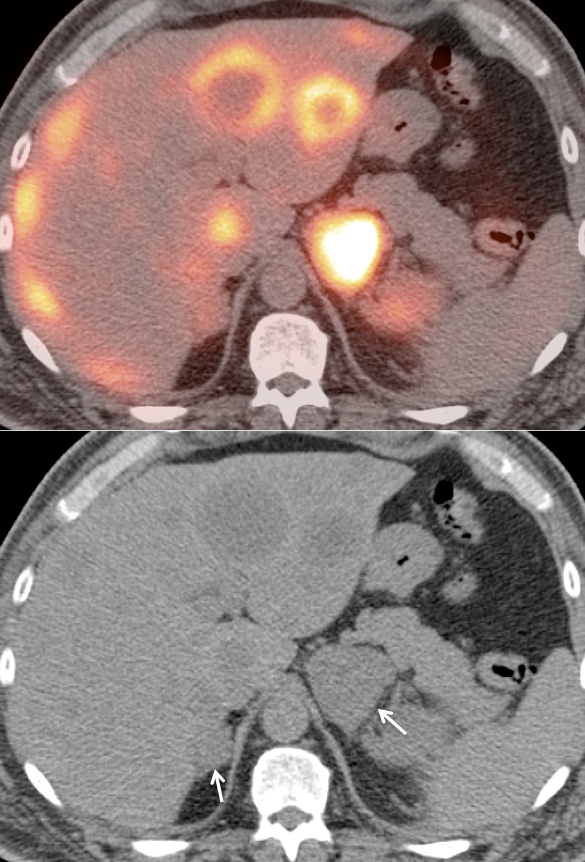

1. FDG is excreted and accumulates in the kidney, easily masking areas of pathologic uptake.

2. Many renal cell carcinomas are only mildly FDG-avid.

3. Nearly every PET/CT scan is performed without intravenous contrast, markedly limiting evaluation of the kidneys on the CT portion of the exam.

• These 3 limitations lead to a sensitivity of only ≈ 60% for the detection of a primary RCCA lesion.

Metastatic Disease: Metastatic RCCA lesions are usually more FDG avid than the primary lesion (nearly all demonstrate metabolic activity greater than liver uptake).

• Lesion masked by normal urine activity

Common: Pooling of FDG-avid urine in a renal calyx.